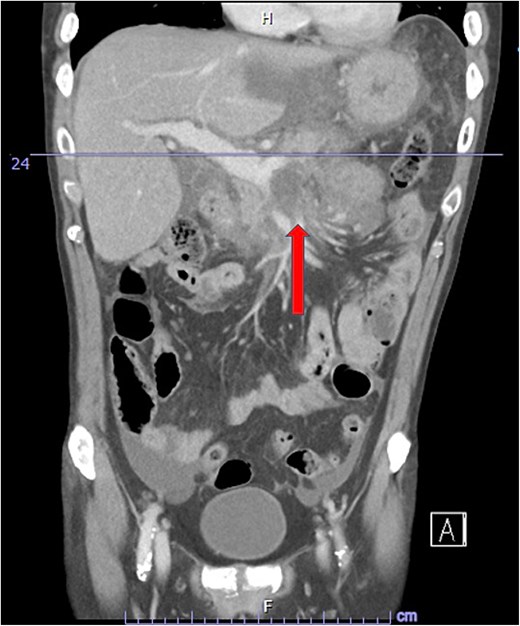

Despite the absence of abdominal symptoms, a computed tomography of the abdomen and pelvis (CTAP) was performed due to markedly elevated lipase levels. The CTAP (Figs 3–5) revealed evidence of acute pancreatitis (Fig. 5, arrow), with a complex peripancreatic fluid collection (Fig. 3, arrow). Additionally, a focal thrombus was observed within the portal venous confluence (Fig. 4, arrow). Further ultrasound of the gallbladder was negative for gallstones (Fig. 6), ruling out gallstone-induced pancreatitis.

CTAP coronal view; complex peripancreatic fluid collection (arrow) with extension behind the splenic vein to lie adjacent to the pancreatic neck and uncinate process.